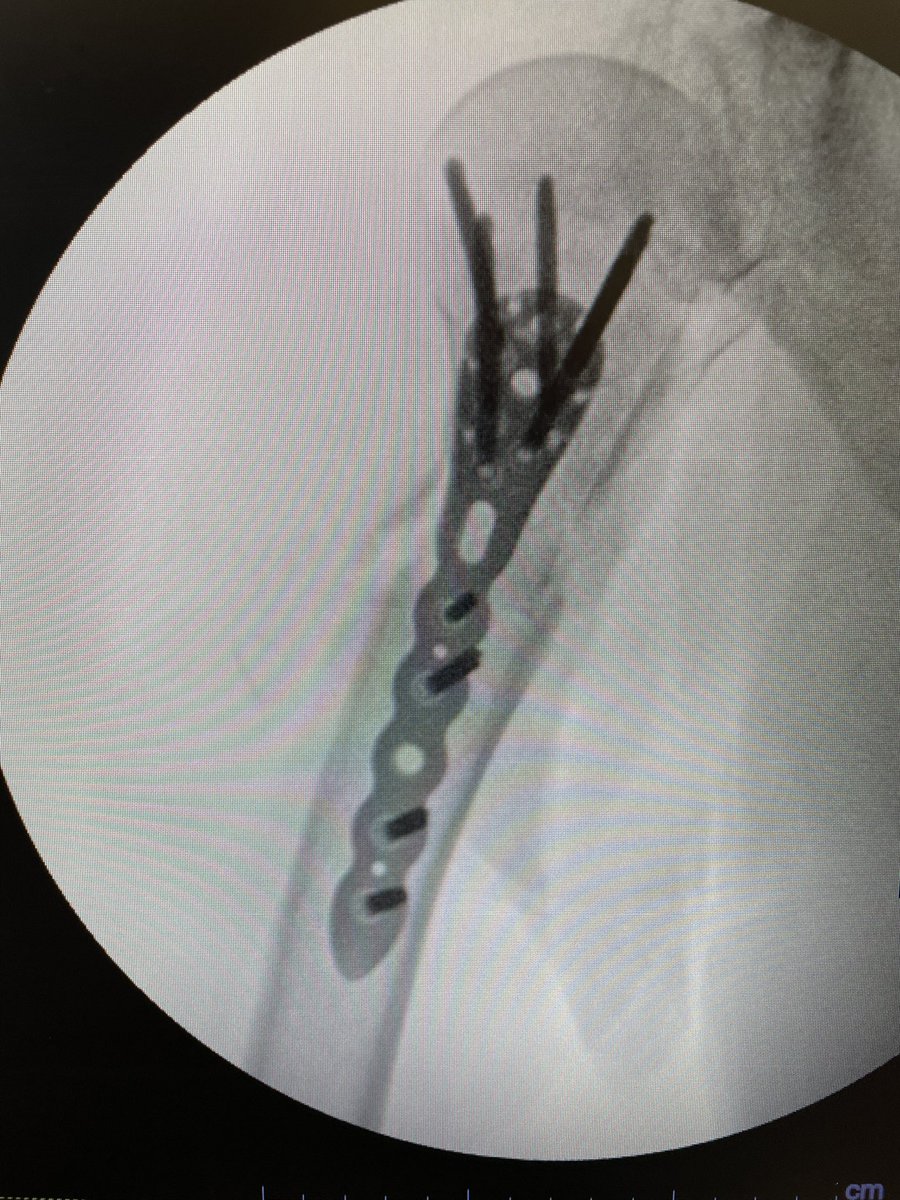

Day 2, case 2: infected femur non-union with shortening. Plan: debridement and irrigation with hardware removal. Circular external fixation for deformity correction and treatment of non-union. Will accept shortening for now.

@MirnaOchoa13 @RiceOlivia